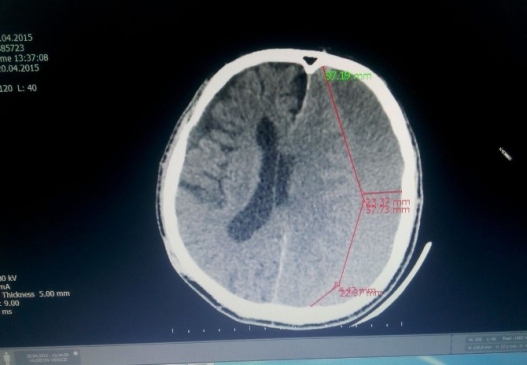

Balıkesir’in Edremit ilçesinde bir ay önce düşerek beyin kanaması geçiren 70 yaşındaki Hüseyin Yenice, fenalaşınca hastaneye kaldırıldı. Hastanın beyin kanaması olduğu ve beyninde kan biriktiği belirlendi. Kalp rahatsızlığı nedeniyle genel anestezi uygulanamayan hasta, lokal anestezi ile ameliyat edildi. Ameliyat öncesinde konuşma yeteneğini kaybeden ve sağ tarafı felç olan Yenice, ameliyattan sonra konuşarak çıktı. Felç durumu ise zamanla iyileşmeye başladı.

Beyin Cerrahi Uzmanı Dr. Cengiz Tekin, operasyon hakkında bilgi vererek, “Hastamız bir ay kadar önce düştü. Sağ tarafında felç gelişti ve daha sonra konuşma yeteneğini kaybetti. İlk olarak özel bir hastaneye gitti, oradan bizim hastanemize beyin kanaması nedeniyle sevk edildi. Kanamasını gördük. 70 yaşındaki hastanın kalbinde ritim bozukluğu ve kalp yetmezliği var. Bu nedenle ameliyata alamadık, anestezi buna izin vermedi. Hastayı uyutmadan lokal anestezi ile kafa tasını açtım ve oradaki kanı boşalttım. Yaklaşık 250 cc kan vardı. Şu anda hastamız konuşuyor ve sağ tarafındaki felç de düzelmeye başladı.” dedi.